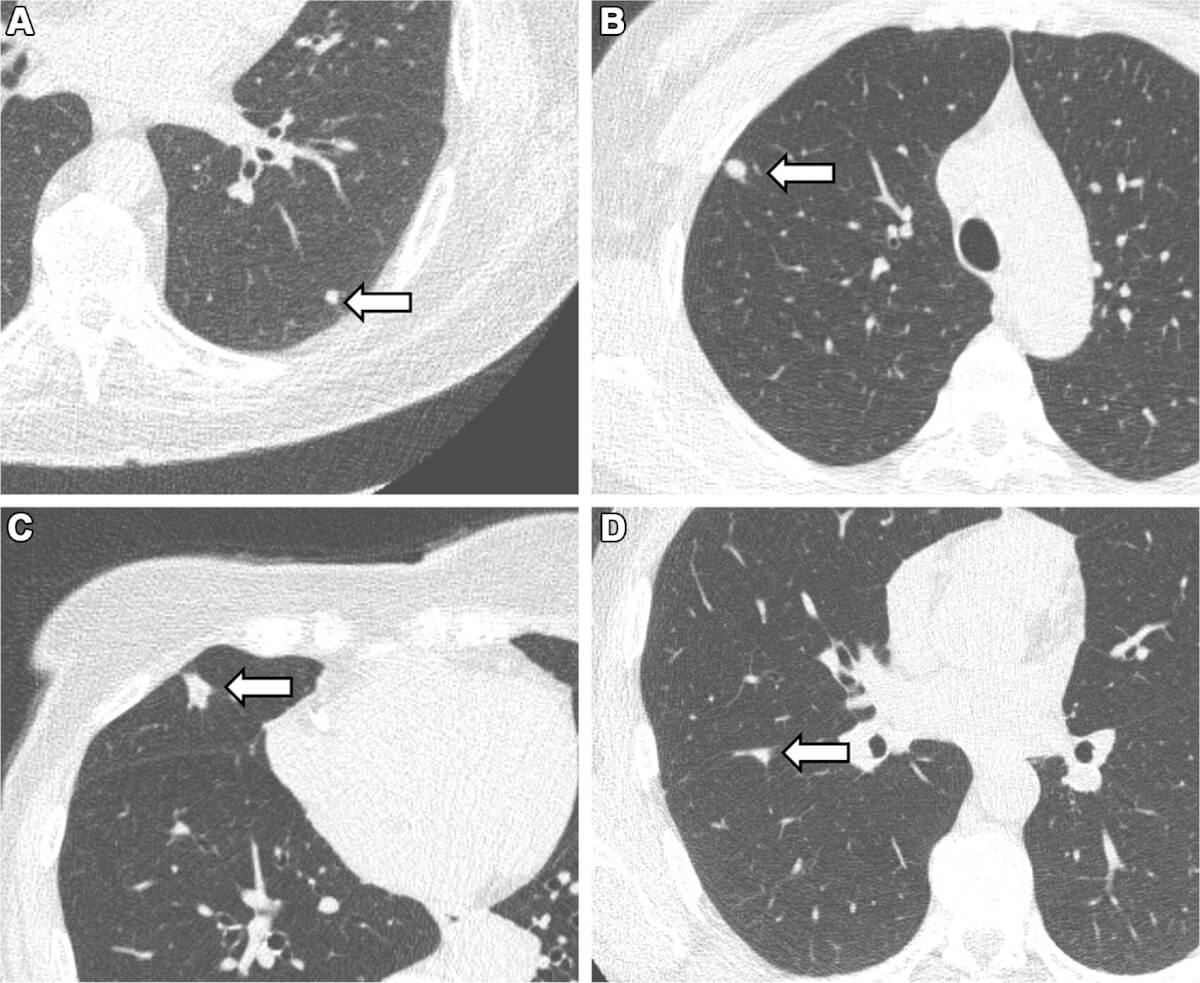

به نقل از اساف، گرهکهای ریه ساختارهای کوچک و گردی در بافت ریه هستند. در حالی که بیشتر آنها خوش خیم هستند، برخی میتوانند نشانههای اولیه سرطان ریه باشند. به طور سنتی، این گرهکها با سیگار کشیدن مرتبط بودهاند و بیشتر درک ما از شیوع آنها از مطالعات افراد به شدت سیگاری یا افرادی که در معرض خطر بالای سرطان ریه هستند، ناشی میشود.

در این مطالعه بیش از ۱۰ هزار شرکتکننده از شمال هلند حضور داشتند که همگی یا قبلا سیگاری بودند یا هرگز سیگار نکشیده بودند. با استفاده از سی تی اسکن محققان توانستند گرهکهای ریه را به قطر ۳.۹ میلیمتر تشخیص دهند.